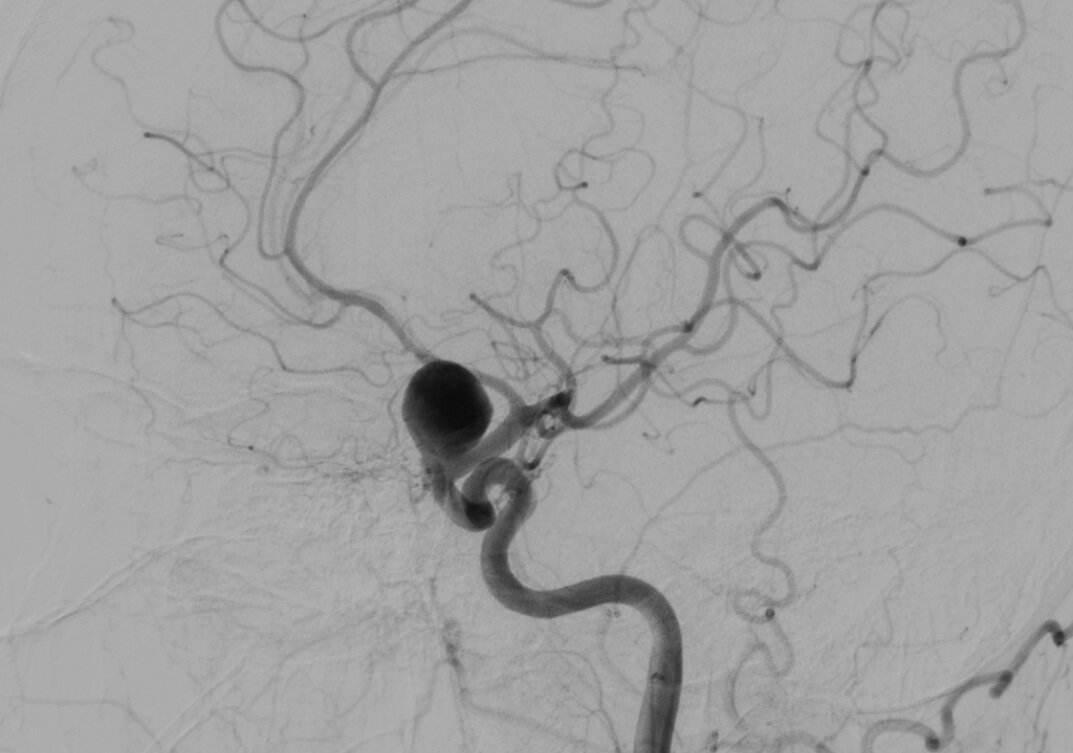

Аневризма - патология, в результате которой происходит выпячивание стенки сосуда из за нарушения его строения.

Со временем стенка сосуда растягивается больше и больше из за чего происходит разрыв, дальнейший участок по ходу сосуда не кровоснабжается, а вытекшая кровь образует гематому, которая в свою очередь сдавливает мозг. Это очень опасное неотложное состояние, при котором требуется скорейшая госпитализация и оказание квалифицированной медицинской помощи.